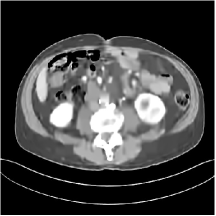

III.B.2. Simulation Framework and Visual Results

We simulate low-dose CT measurements using XCAT phantom slices with mm. The generated sinograms are of size , obtained with GE 2D LightSpeed fan-beam geometry corresponding to a monoenergetic source with incident photons per ray and no scatter. For PWLS-EP, we ran iterations of the relaxed LALM algorithm with the FBP reconstruction as initialization and regularization parameter . For the MARS model, we used the relaxed LALM algorithm for the image update step with inner iterations. We initialized PWLS-MARS schemes with the PWLS-EP reconstruction and used outer iterations for ST and all MARS schemes.

We firstly hand-tuned the reconstruction parameters () for one test slice and treated this set of parameters as the baseline. Similar to the PWLS-EP algorithm, we could determine the optimal (in terms of optimal RMSE) parameters for other testing slices by tuning the base parameters in a small range. However, we found that the change in reconstruction quality by picking a common set of parameters instead of slice-wise optimized parameters is quite small (only 0.2 HU in RMSE and without the loss of details). Therefore, the same set of parameters (baseline parameters) were used across testing cases and shown to be effective over the cases. In particular, we selected slice 48 of the XCAT phantom as the case for parameter tuning and set the regularization parameters (after tuning over ranges of values) as , , for ST, , , , , for MARS2, , , , , , , for MARS3, , , , , , , , , , , for MARS5, and , , , , , , , , , , , , , , for MARS7, respectively. In Fig. 14 in the supplement, we give the reconstructions for slice 48 of the XCAT phantom with various methods. Figs. 4 and 5 here show the reconstructions for two independent test cases (slice 20 and 60 of the XCAT phantom). Both of them used the same set of parameters obtained for slice 48. The zoom-in regions give an explicit comparison between the multi-layer sparsifying transform models and other methods such as FBP, PWLS-EP, and PWLS-ST. PWLS-MARS achieves better noise reduction and higher contrast.